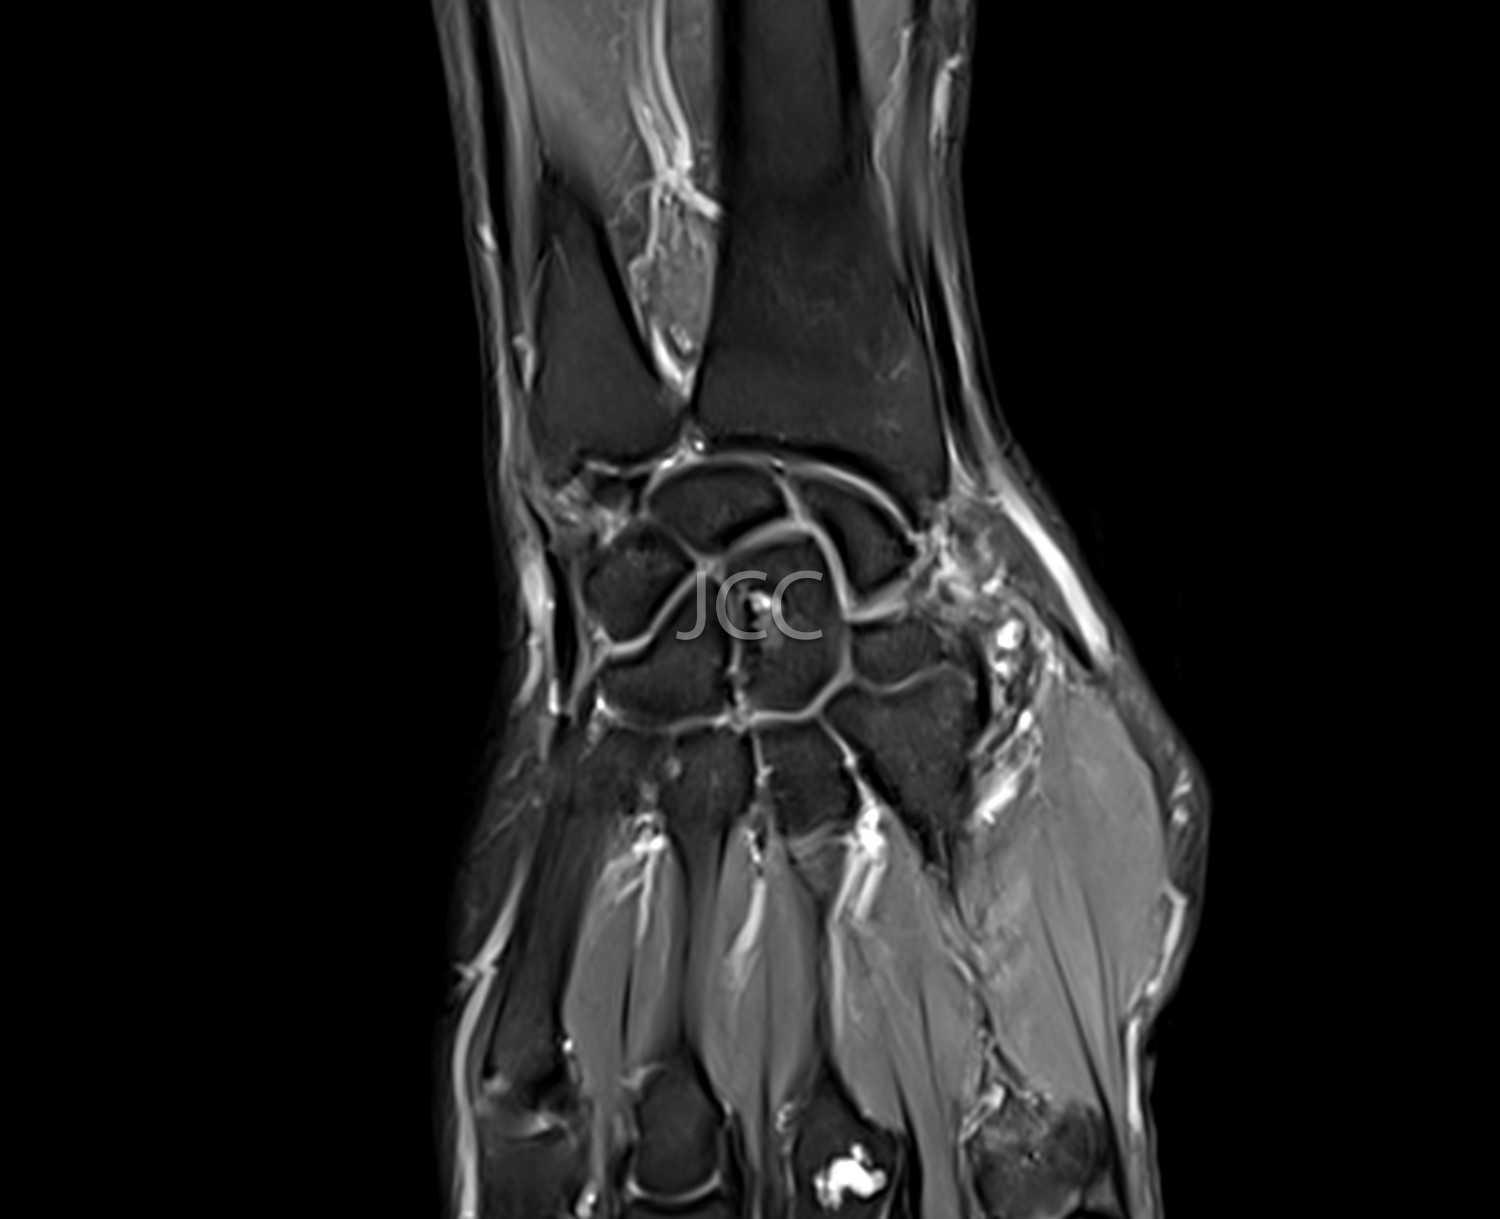

Ressonância Magnética de Alto Campo - RM Osteo-Articular

A Ressonância Magnética de Alto Campo é uma técnica de imagem que não utiliza radiação baseando-se num campo magnético e ondas de radiofrequência para estudar detalhadamente os órgãos do corpo humano.